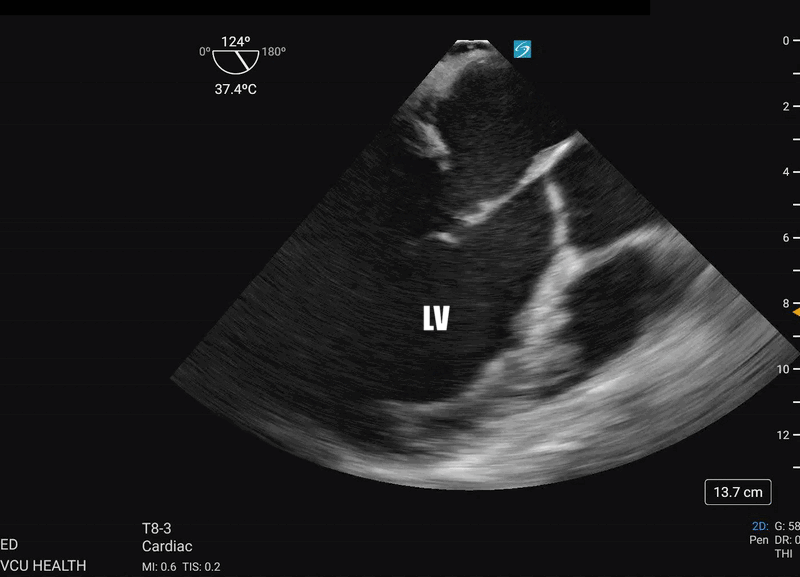

The TEE mid-esophageal long axis view (ME-LAX) is the mirror image of the parasternal long axis view in transthoracic echo (TTE), with the left atrium closest to the probe face and the right ventricle (RV) furthest from the probe. To achieve this view, the TEE probe is inserted approximately 30-35cm until a mid-esophageal four chamber view is obtained. From this starting point, the omniplane is rotated to 120 degrees, then further fine adjustments are made to the omniplane and probe rotation until a view showing both mitral inflow and aortic outflow to the left ventricle (LV) is achieved (Fig. 1). This view is excellent for evaluating LV contractility and assessing aortic and mitral valve function.1 During resuscitation, this view is key to real-time evaluation of CPR effectiveness.

Figure 1. TEE ME-LAX view showing severely reduced ejection fraction (EF) following ROSC

The ME-LAX view is important for evaluating left ventricular size and function when assessing for heart failure or ischemic disease.2 The view helps assess the dimensions of left ventricle, evaluation of wall motion abnormalities, estimation of ejection fraction, and is important for evaluating the ventricular contractility.1